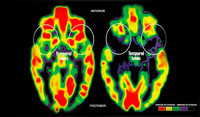

DesarrolloEl cerebro de los bebés es un mundo asombroso por descubrir. Las conexiones neuronales que se establecen en los primeros años de vida dejan una huella imborrable, también en lo relacionado con el idioma. Según un estudio reciente...